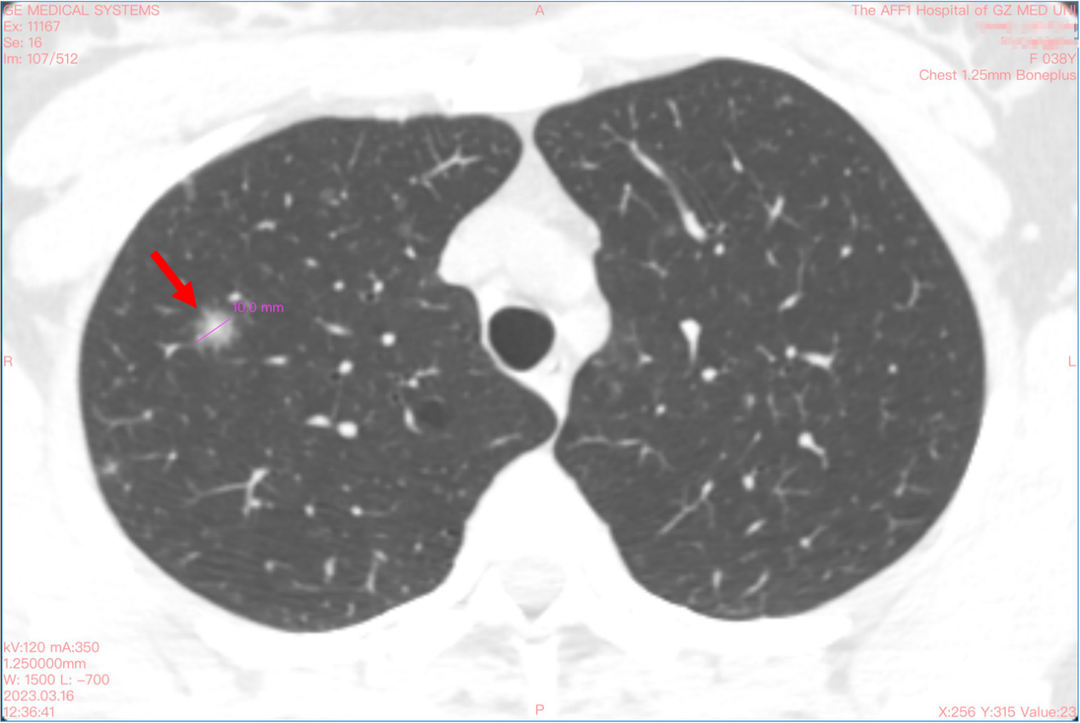

我们身体里的隐患如同定时炸弹,会给生活带来巨大的危机。而对小雨来说,这颗炸弹引爆得太早了。2022年,37岁的小雨体检发现双肺有多发结节,数量多达200余个,其中最大的结节位于右上肺,直径大小约为10mm。2023年体检的胸部CT结果提示,右上肺结节实性成份较前增加。

治疗中,团队先使用机器人辅助导航系统进行了CT引导下的穿刺活检,成功获取了病理组织标本,确诊右上肺结节为肺腺癌。